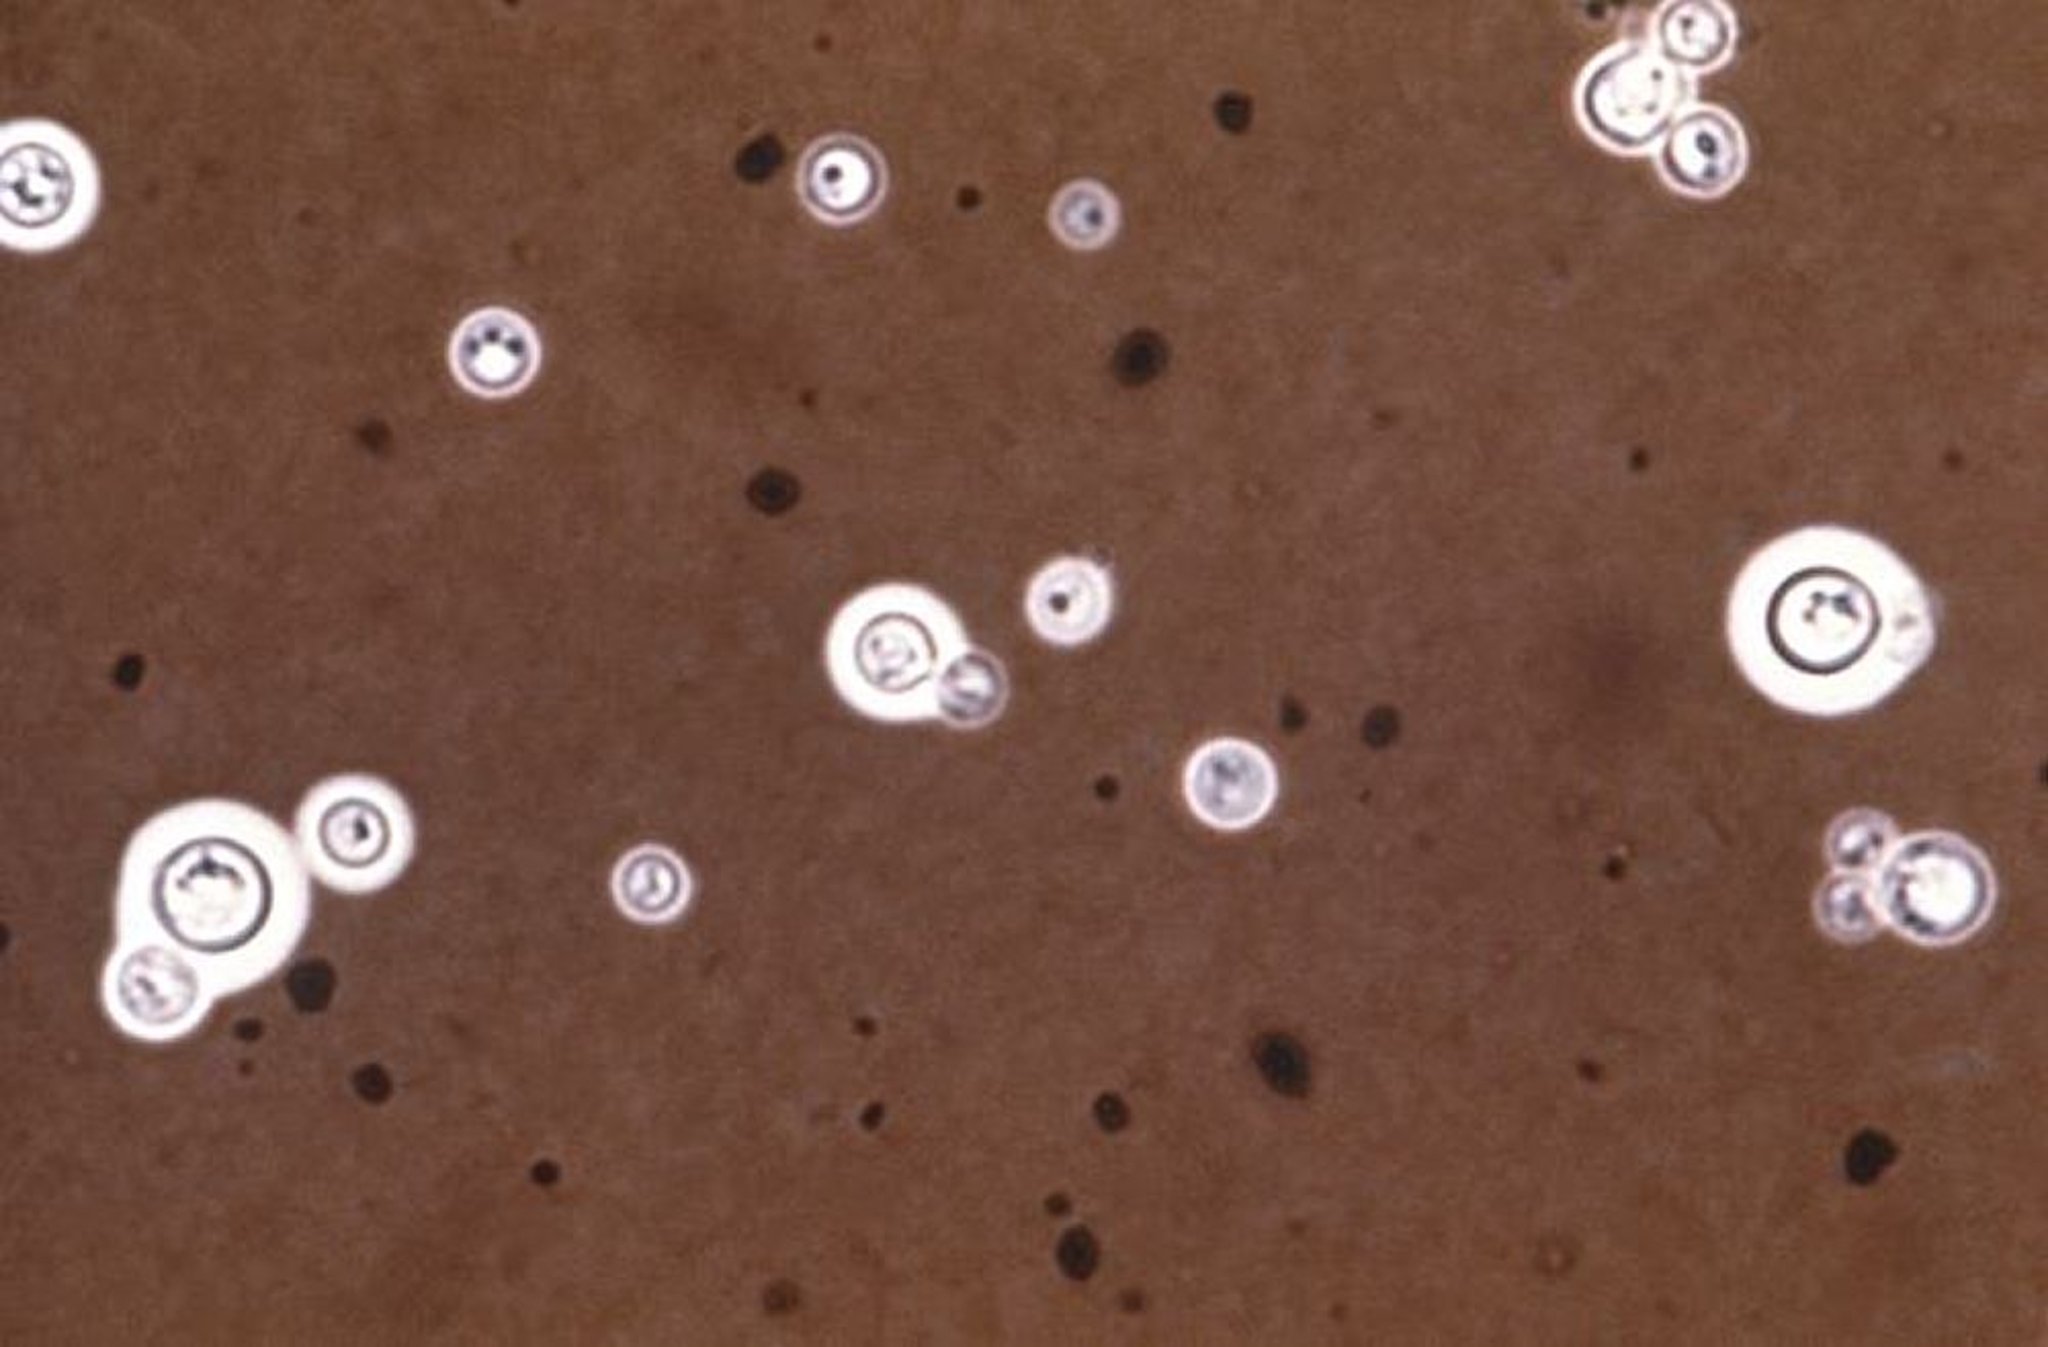

Coloration à l'encre de Chine (pour Cryptococcus neoformans)

Cette image est une micrographie optique de C. neoformans coloré à l'encre de Chine. La coloration à l'encre de Chine rend les capsules autour des microrganismes visibles sous la forme d'un halo (anneau lumineux).